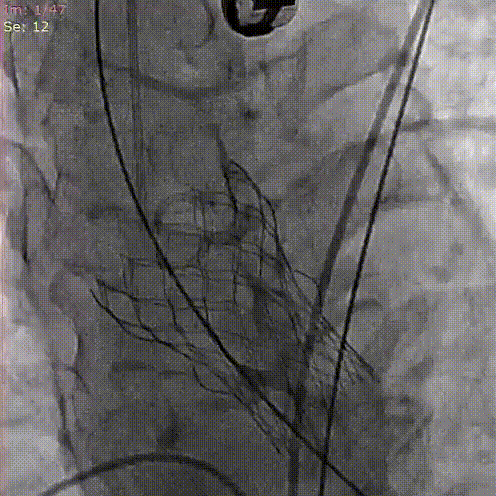

C. 应用交界贴合技术调整人工瓣膜,输送系统内支架最下缘平齐标准位释放瓣膜

D. 瓣膜释放后造影

C. 应用交界贴合技术调整人工瓣膜,标准位释放瓣膜并行释放后造影

D. 瓣膜释放后造影显示瓣膜位置良好